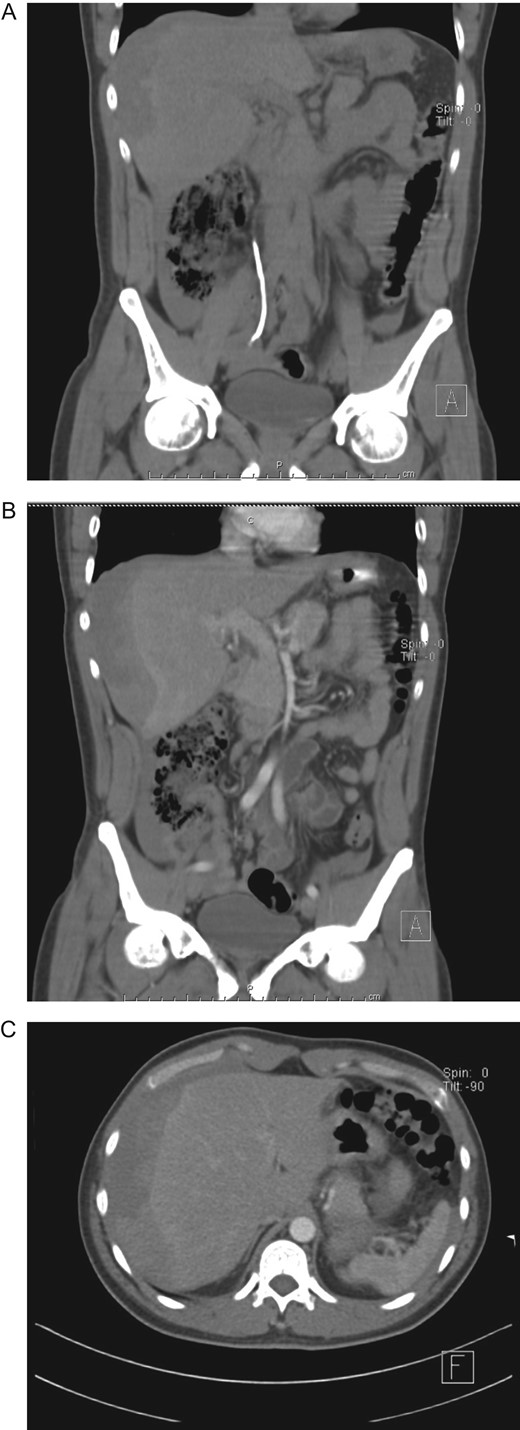

Blood transfusion was not required and after 7 days of conservative therapy, as the patient was completely asymptomatic and his hemoglobin remained stable, he was discharged. On follow-up controls patient is doing well, without any pain, his last Hb was 11 g/dl and a remarkable reduction of the hematoma was seen on a new CT scan.